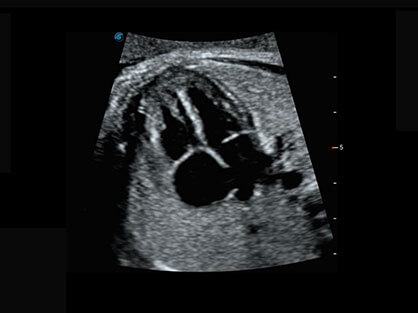

作为P系列家族成员之一,P40 Plus采用百老汇电子游戏官网高端超声系统平台——极光,并以时尚秀丽、小巧灵动的外观设计绽放出灵动之韵、科技之美。高端平台的使用保证了P40 Plus优质的基础图像;完备的高级功能可满足您全身应用的基本需求;丰富的探头配置、多样的高级4D成像及分析软件为您日益增多的妇产应用需求提供丰富的诊疗方案。